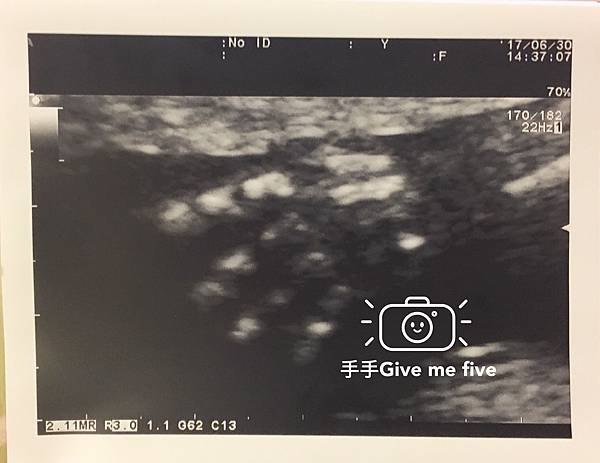

26週超音波+妊娠糖尿病篩檢

寶貝超喜歡把手手放在臉上